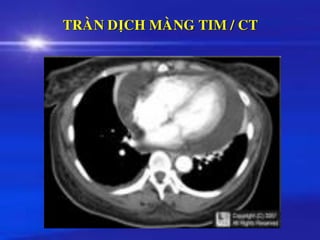

➢ Chaån ñoaùn dòch MNT hay daày maøng tim:

Thoâng tim Chuïp caét lôùp ñieän toaùn

Quang taâm maïch MRI

TRAØN DÒCH MAØNG TIM / CT